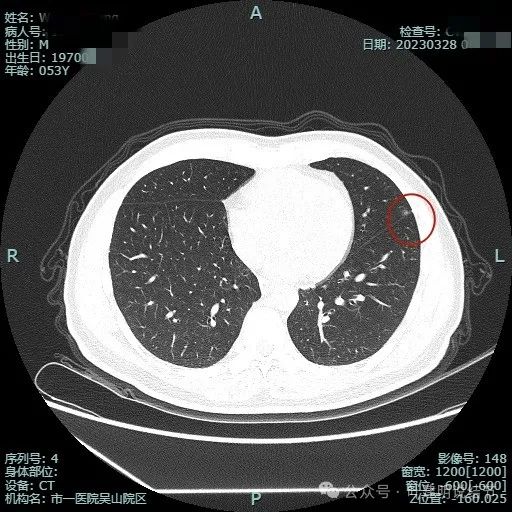

2023年3月影像展示:

上图显得瘤肺边界稍模糊。

病灶似有极微细血管进入,贴着叶间胸膜但没有牵拉或明显凹陷。